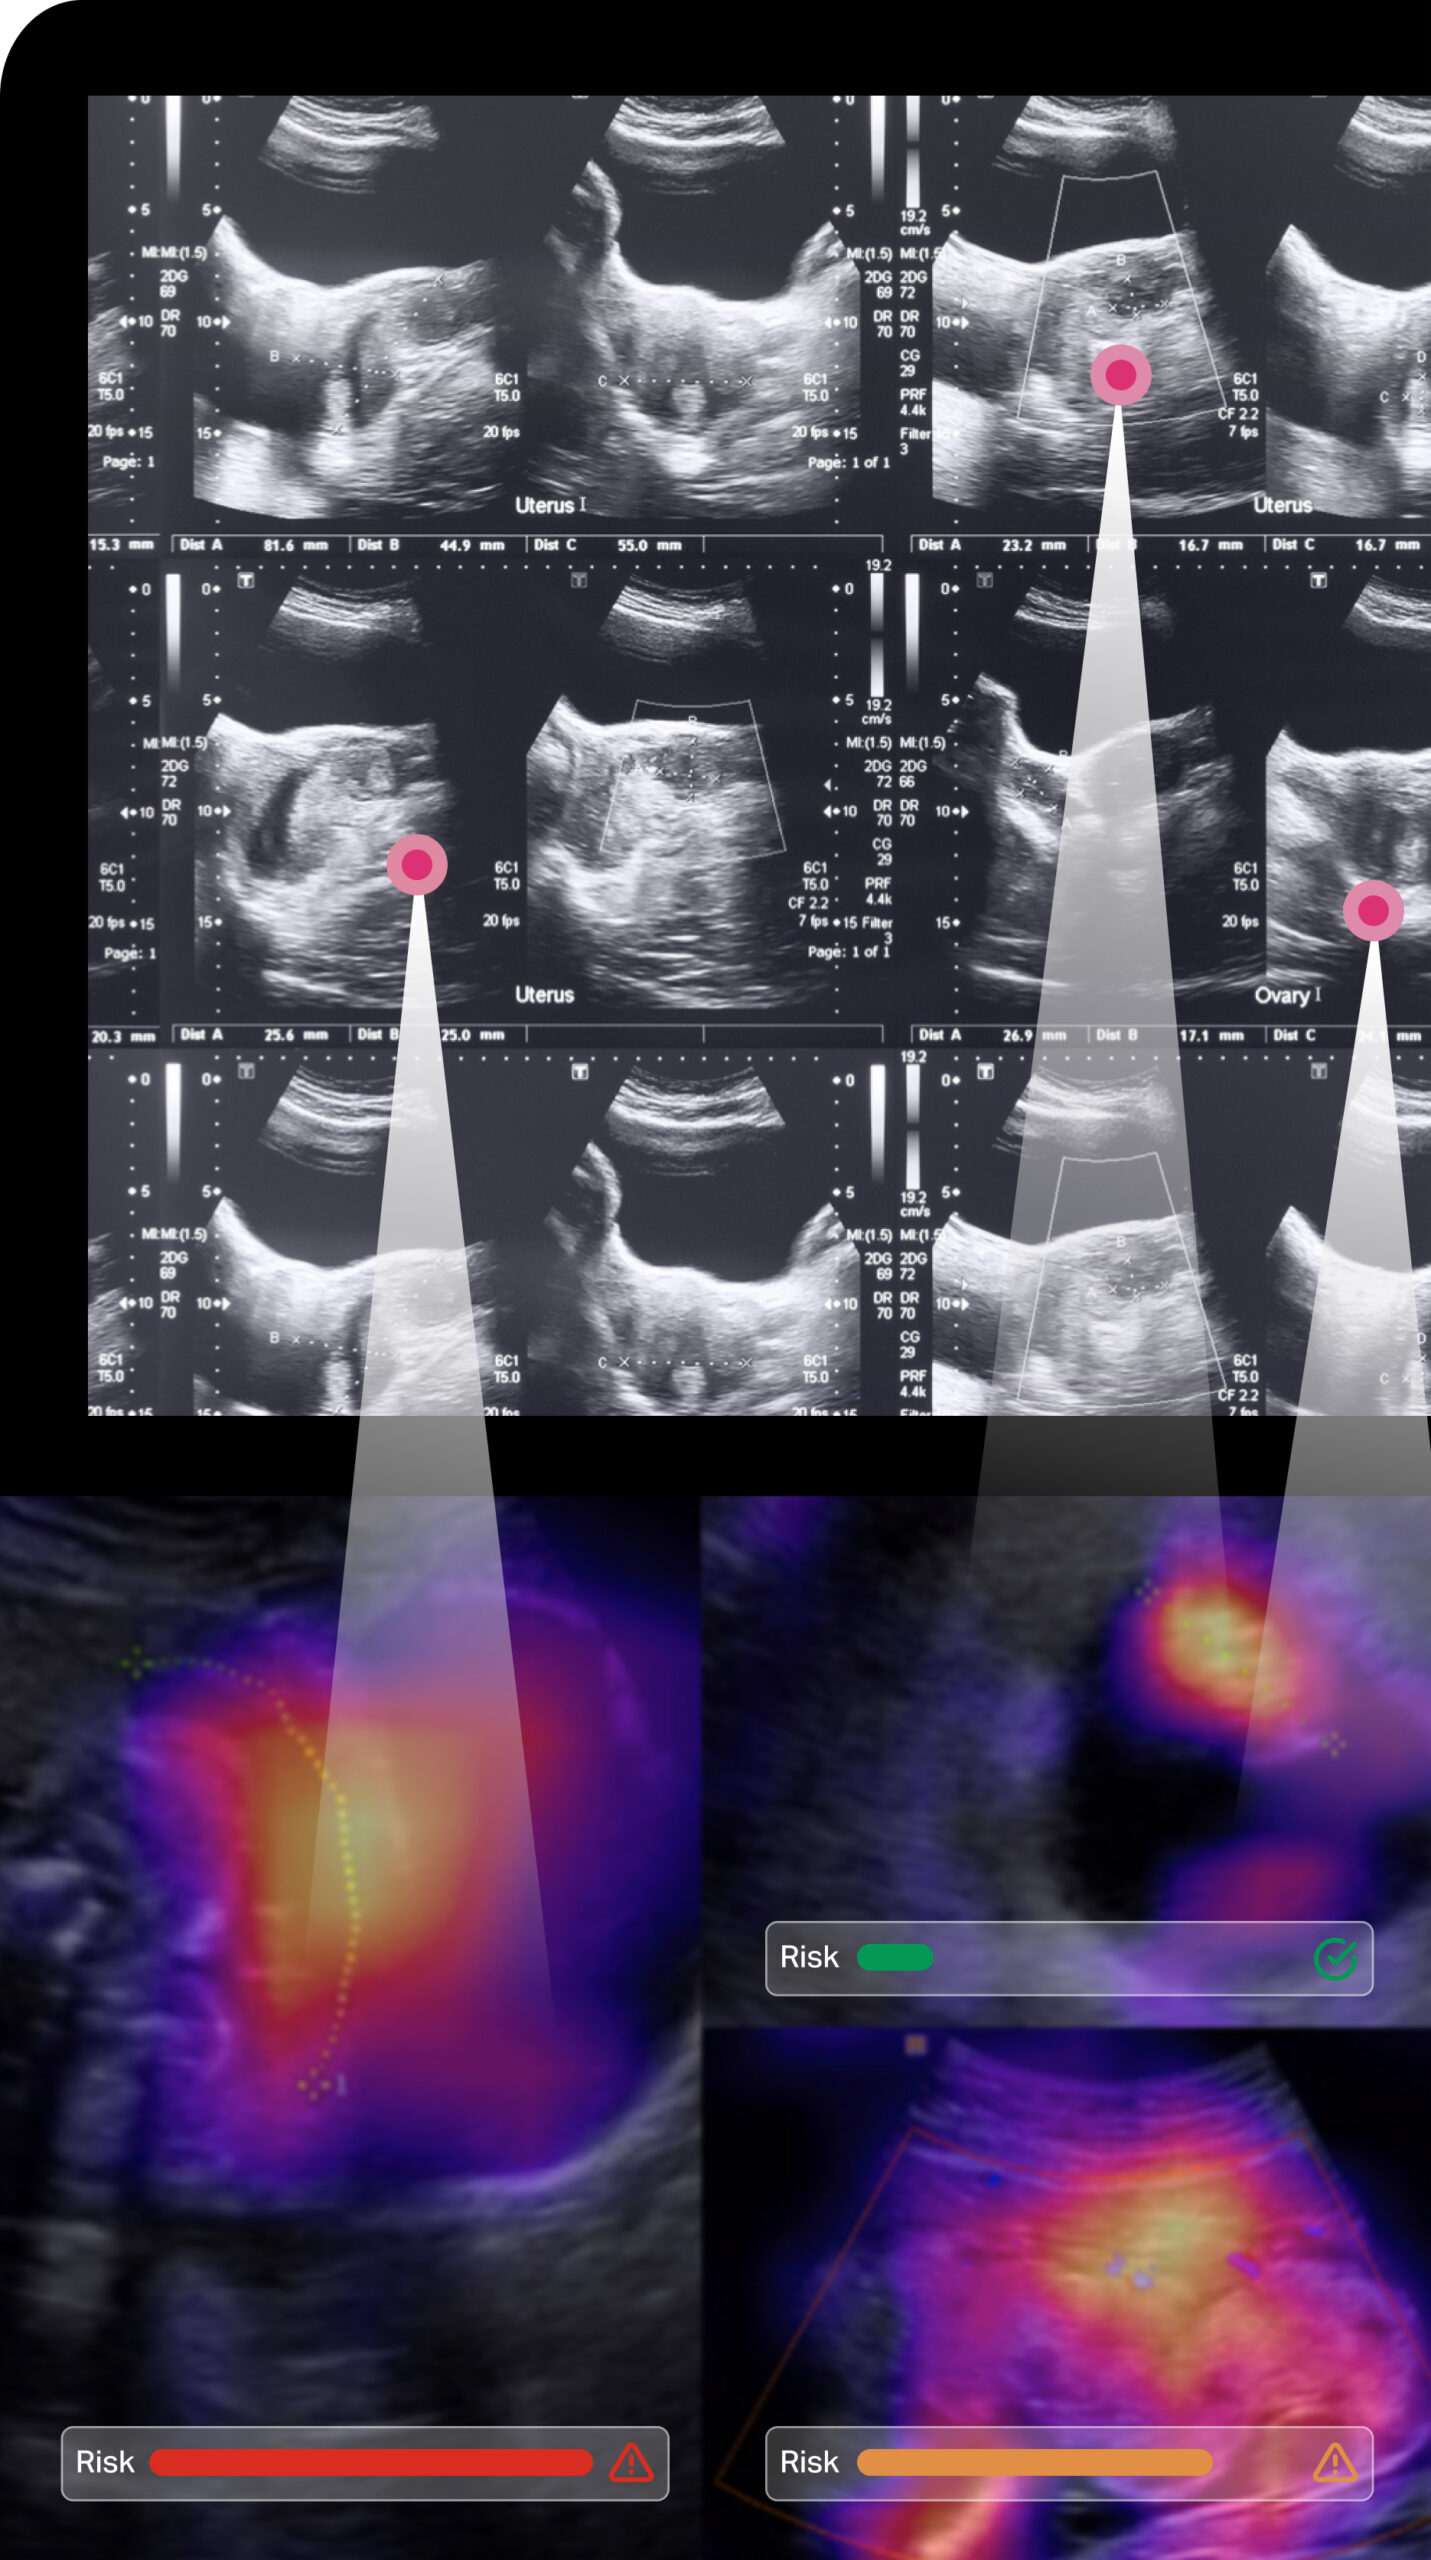

Preterm AI, our first product, has been trained by over four million ultrasound images using advanced neural networks. It has the potential to radically change prenatal care by identifying those women at risk for preterm labor who would have been missed and giving providers near-instant and updated feedback on their patients’ statuses with regards to specific disease processes.

The Preterm AI platform empowers clinicians to improve outcomes.